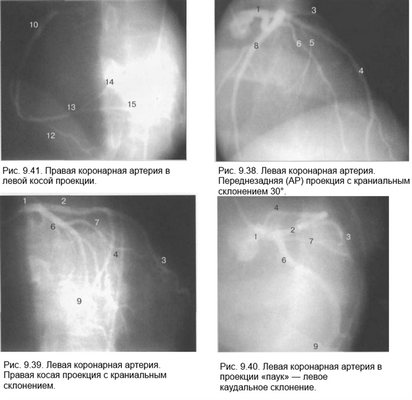

Рис. 9.37. Левая коронарная артерия. Правая косая проекция.

Здесь и на рис. 9.38—9.46:

1 — левая коронарная артерия; 2 — проксимальная треть передней нисходящей артерии; 3 — первая диагональная ветвь передней нисходящей артерии; 4 — дистальная часть передней нисходящей артерии; 5 — септальная ветвь передней нисходящей артерии; 6 — проксимальная часть огибающей артерии; 7 — первая маргинальная ветвь огибающей артерии; 8 — промежуточная артерия; 9 — дистальная часть огибающей артерии; 10 — проксимальная часть правой коронарной артерии; 11 — ветвь синусного узла правой коронарной артерии; 12 — ветвь острого края правой коронарной артерии; 13 — бифуркация правой коронарной артерии; 14 — правая левожелудочковая ветвь правой коронарной артерии; 15 — задняя нисходящая ветвь правой коронарной артерии.

Фиксация изображения коронарных артерий производится последовательно в нескольких плоскостях.

На рис. 9.37—9.41 изображены левая и правая коронарные артерии и их ветви при равномерном типе коронарного кровообращения в обычной последовательности проекций.

На следующих рисунках представлены два типа коронарного кровообращения — правый и левый и характеризующиеся неравномерным развитием правой коронарной и огибающей (ветвь левой коронарной артерии) артерий. При левом типе отмечается выраженная периферия огибающей артерии при значительной гипоплазии правой коронарной артерии. При правом типе чаще всего хорошо развита маргинальная ветвь и гипоплазирована основная ветвь огибающей артерии. Периферия правой коронарной и, в особенности, правая левожелудочковая ветвь значительно выражены и превосходят огибающую по размерам зоны кровоснабжения.